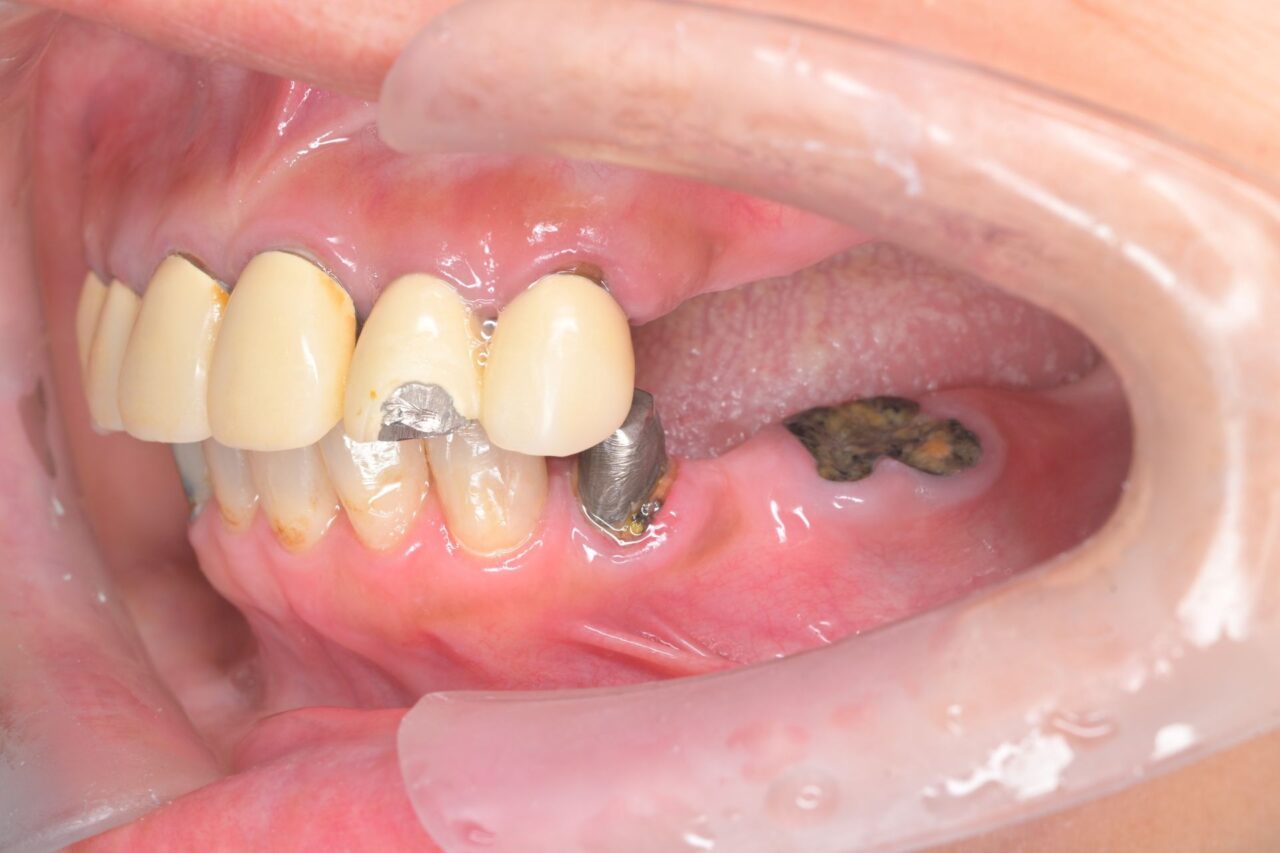

上面

前歯をつなげっちゃっていて、フロスの使用が困難な補綴物が入っています。

毎度おなじみの全部交換です。